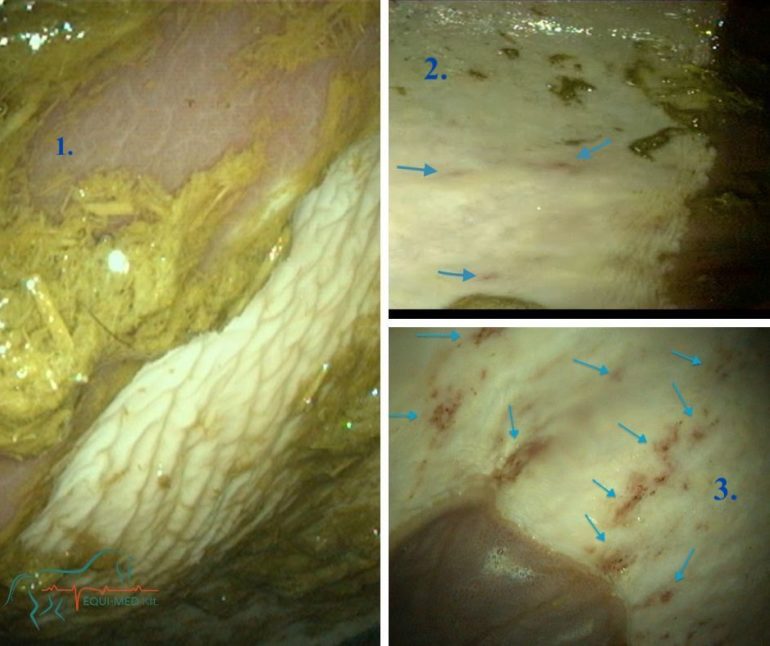

Egy másik korszakalkotó eszköz a digitális mobil endoszkóp, ami a légutak vizsgálatán kívül a gyomor, a nyelőcső és patkóbél első szakaszának vizualizálására is használható. Ehhez azonban hosszabb, 3 méter hosszú eszköz szükséges. A gasztroszkópia (gyomortükrözés) az egyetlen mód jelenleg, amellyel a gyomorfekély diagnosztizálható. Tévhit az, hogy a vizsgálatot megelőző 16-18 órás éheztetés problémát okozna lónak, viszont egy nem diagnosztizált fekély számos súlyos probléma forrása lehet, a diagnózis nélküli kezelés pedig drága és hatékonysága ellenőrizhetetlen.